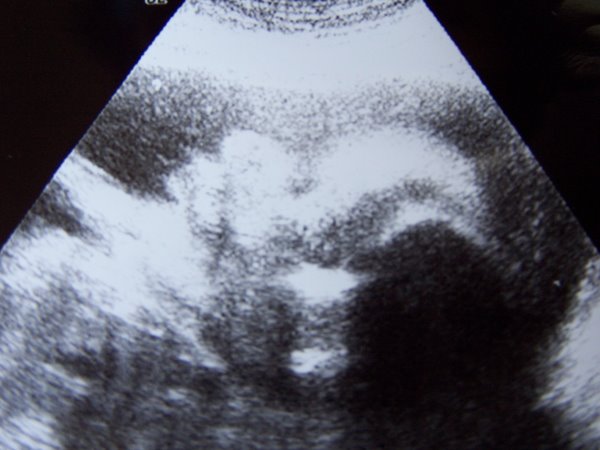

Teszek fel két képet, amik a tegnapi uh-n készültek.

Az elsőn Zsófi arca látszik szemből (megjegyzem, hogy ez az első alkalom a 32 hét alatt, hogy sikerült elkapni valami részletet az arcocskájából)

Kép